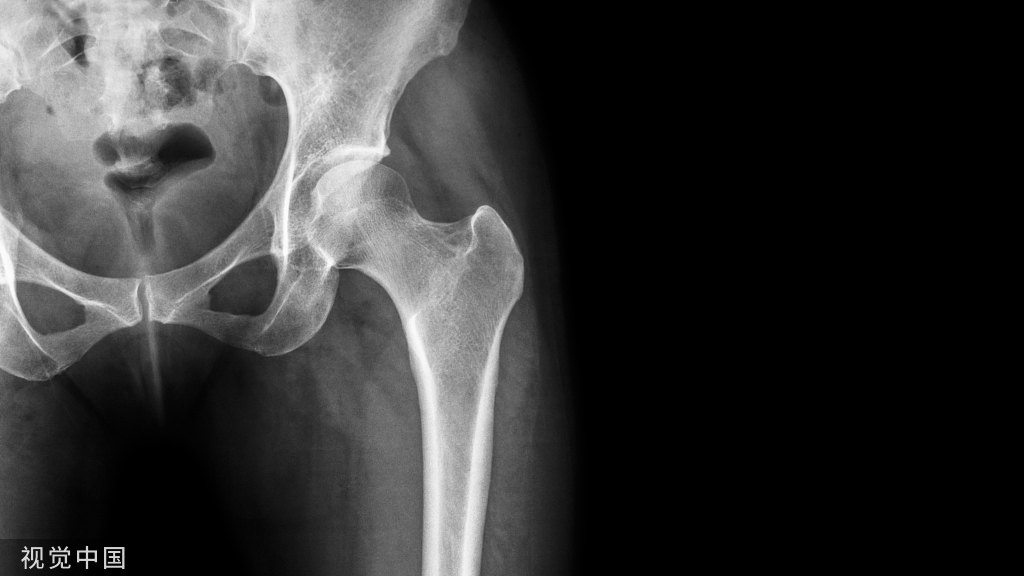

13、疾病影响很多情况下,半月板并没有损伤,而且由于疾病的影响,例如痛风性关节炎导致半月板的表面出现痛风结晶沉积,或者关节内的痛风石将半月板推离正常的位置等等,由此MR上出现半月板的信号甚至形态发生改变,半月板本身不一定真正出现损伤。